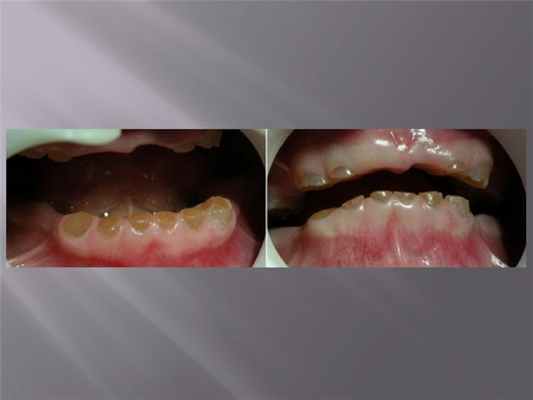

При II типе дисплазии дентина поражаются молочные и постоянные зубы, но гистологические изменения в них, клиническая и рентгенологическая картина отличаются. По своим гистологическим и клиническим особенностям изменения в молочных зубах напоминают незавершённый дентиногенез, зубы полупрозрачны и похожи на янтарь. На рентгенограммах коронки имеют форму луковицы, тонкие конические корни; как и при незавершённом дентиногенезе, характерна ранняя облитерация пульпарной полости. При гистологическом исследовании постоянных зубов выявляют интерглобулярный дентин в коронке, камни в пульпарной полости и патологически изменённый дентин в области корня, не содержащий дентинных трубочек. Хотя постоянные зубы обычно имеют нормальный цвет, но большие, чем в норме размеры; в случае, представленном на рисунке, отмечают слабую опалесценцию и янтарный оттенок, которые особенно выражены у нижних зубов и напоминают незавершённый дентиногенез; верхние медиальные резцы несколько увеличены. На приведённой рентгенограмме отмечают типичную картину: изменение формы полости зуба, наличие дентиклеи, узкий корневой канал, напоминающий стебель осота. Поражённые зубы выпадают реже из-за отсутствия тенденции к спонтанному воспалительному процессу, приводящему к изменениям в периапикальной зоне.